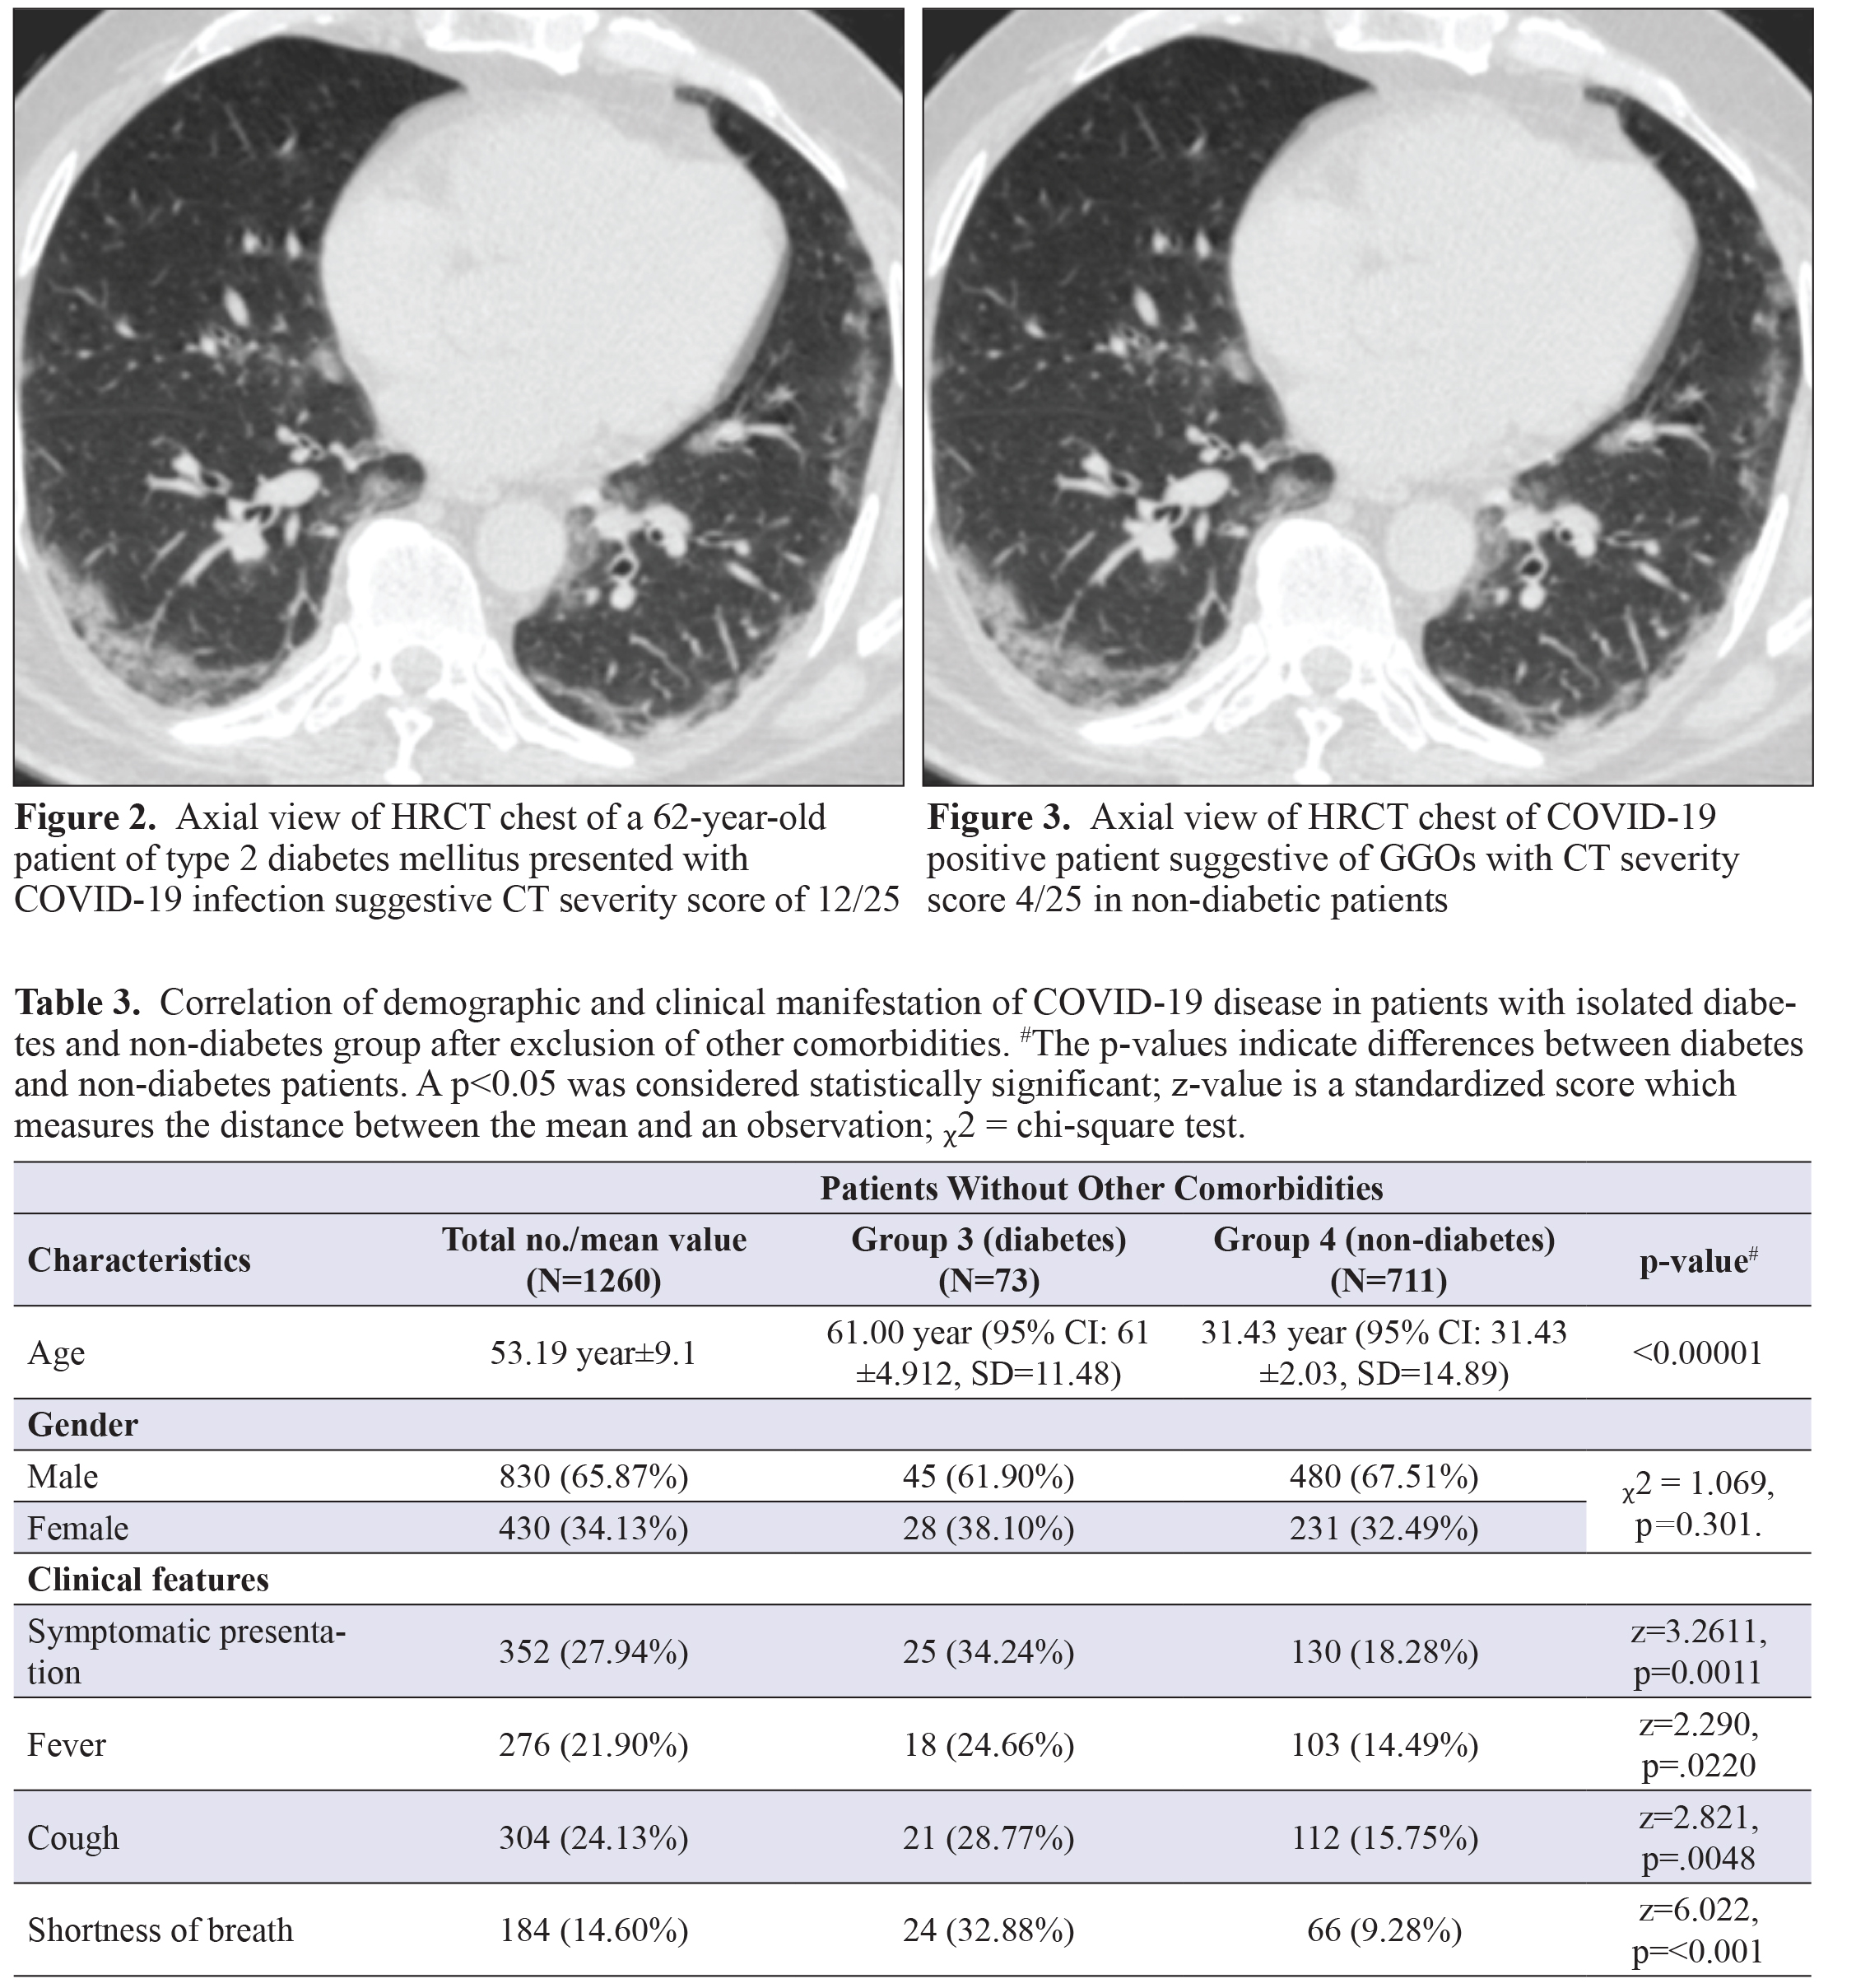

The mean age of SARS-CoV-2 infected patients without other comorbidities was 53.19±9.1 year. The mean age of thediabetes group (54.08 years) was not significantly higher as compared to that observed in the non-diabetes group (52.95years) (Table 3). The gender distribution did not differ significantly among the groups, where the sex ratio (F: M) was 0.68in the diabetes group and 0.49 in the non-diabetes group without co-morbidities.

Clinical presentation (Table 3):

Among patients devoid of pre-existing comorbidities, 352 patients (27.94%) were symptomatic for COVID-19, thoughonly 22.86% non-diabetic patient were symptomatic as compared to 45.71% symptomatic diabetic patients, a statistically significant difference (p<0.001). COVID-19 infected patients without other comorbidities predominantly presented withfever (21.90%), cough (24.13%), sore throat (18.10%), shortness of breath (14.60%), headache (10.16%), chest pain (4.13%)and other symptoms (3.81%) like pain abdomen, vomiting, diarrhoea, altered sensorium. Clinical presentation with fever(28.57% in Group 3 vs. 20.00% in Group 4), cough (30.36% in Group 3 vs. 22.35% in Group 4), shortness of breath (27.14%in Group 3 vs. 11.02% in Group 4) and headache (13.57% in Group 3 vs. 9.18% in Group 4) was observed significantly higherin the diabetes group compared to the non-diabetes group.

Digital chest radiograph (CXR) of all patients, USG chest of 200 patients (15.87%) and HRCT chest of 424 patients (33.65%)was available for analysis. CXR depicted a classic for COVID images in 208 patients (16.51%) with an average visual score of0.63±0.81 out of 4. USG severity score was 14.88±9.18 out of 14 and average CT severity score was observed to be 5.81±5.44out of 25 with CT severity score >10/25 in 80 patients (18.87%) (Figure 4 and 5). Radiological findings observed amongdiabetes group and non-diabetes group without comorbidities were as follow: The CXR average visual score was 0.74 and 0.58(p=0.0035) while classic for COVID images was observed in 28.57% and 13.06% patients (p<0.001) in Group 3 and Group4 respectively. USG chest severity score was significantly higher in diabetes group (17.86) as compared to the non-diabetesgroup (13.48) (p=0.0041) (Figure 6 and 7). CT severity score was 7.24 in the diabetes group and 5.32 in the non-diabetesgroup (p=0.0020) with a CT severity score >10/25 in 29.41% and 15.53% patients in the respective groups (p=0.0018).